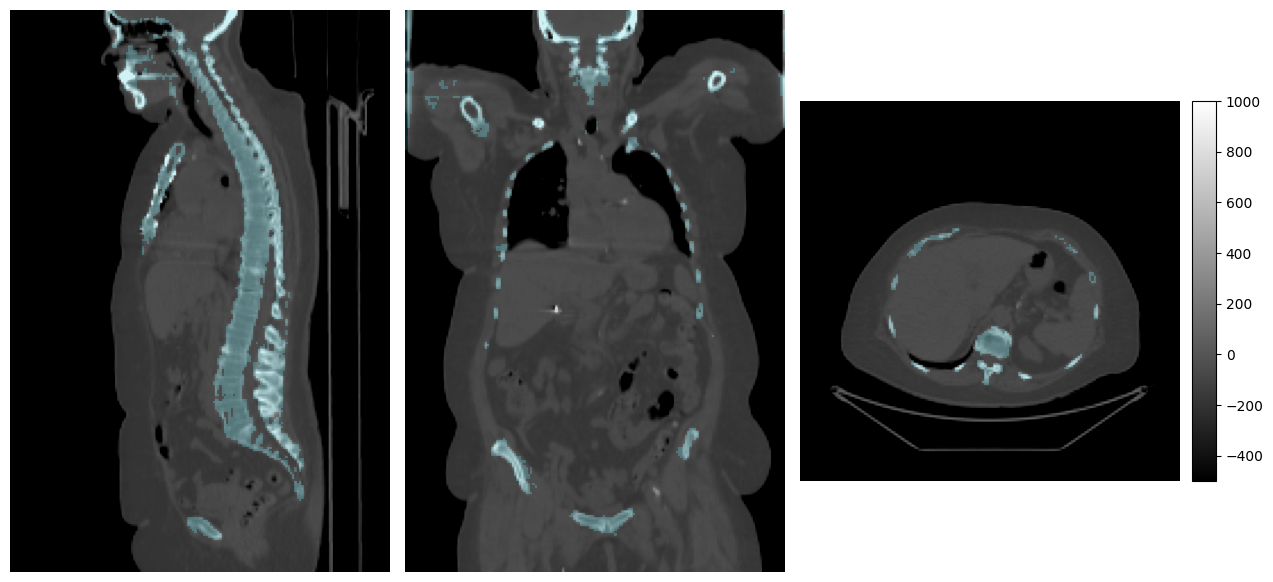

# Loading the images just so we can visualize them here

# This has no relevance to the pipeline that we will construct below

mpr_plot(

imfusion.load(ct_file)[0][0],

labels=imfusion.load(target_file)[0][0],

vmin=-500,

vmax=1000,

label_alpha=0.2

)

../../_images/tutorials_imfusion-sdk_3_building_data_pipelines_4_0.png